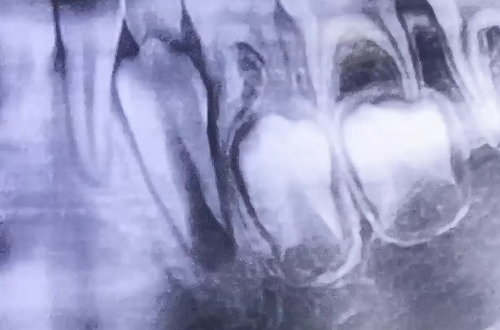

어릴 때 가지고 태어나는 유치가 하나씩 맹출되고 잇몸 속에는 영구치가 묻혀있어, 유치와 영구치가 함께 존재하는 시기를 혼합치열기라고 합니다.

유치는 어떤 과정을 거쳐 빠지게 되는 것인지 그 과정을 포함하여 혼합치열기의 특징은 무엇이 있는지, 어떤 것을 조심해야 하는지 등의 내용을 본원에서 진료 받은 어린이 환자의 엑스레이를 보며 설명해 드립니다!